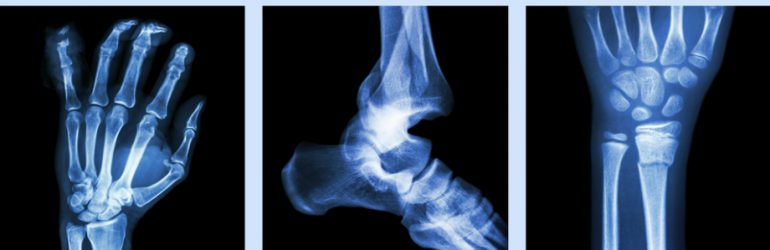

Une équipe néo-zélandaise a examiné les fondements de la recommandation en faveur d’une majoration des apports calciques pour améliorer la santé osseuse et prévenir les fractures. La première étude constate que la majoration calcique par les aliments ou les suppléments entraine une faible augmentation de la densité minérale osseuse (1 à 2%), qui est peu susceptible de conduire à une réduction cliniquement significative du risque de fracture.

La seconde étude conclut, quant à elle, que le calcium alimentaire n’est pas associé au risque de fracture, et qu’il n’y a pas de preuve clinique indiquant que la majoration de l’apport en calcium par les aliments prévient les fractures.